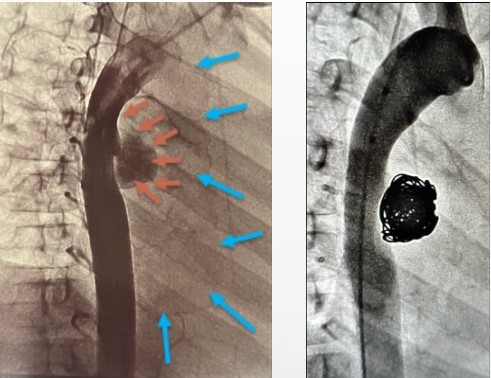

She underwent cardiac catherization, which revealed a large mycotic aneurysm on the descending aorta measuring 18 mm x 15 mm with thrombus around the periphery. The lesion produced a mass effect, compressing the left main bronchus, leading to atelectasis. The pseudoaneurysm was treated via complete coil occlusion to prevent any residual flow to the outpouching sac (Image 3). Following recovery, a repeat chest CT showed improvement of aeration over the left lung field and bronchus.